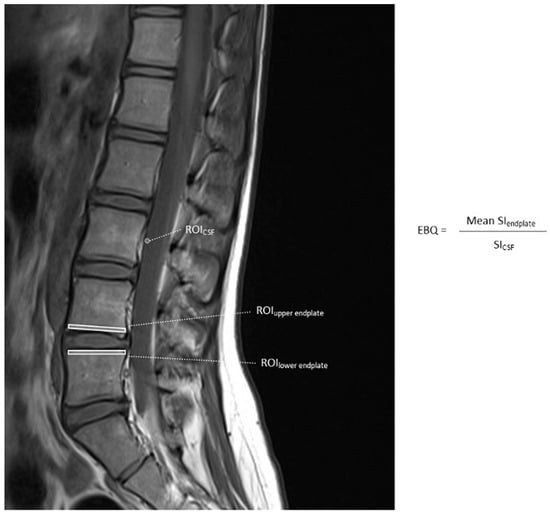

3.2. Endplate Bone Quality